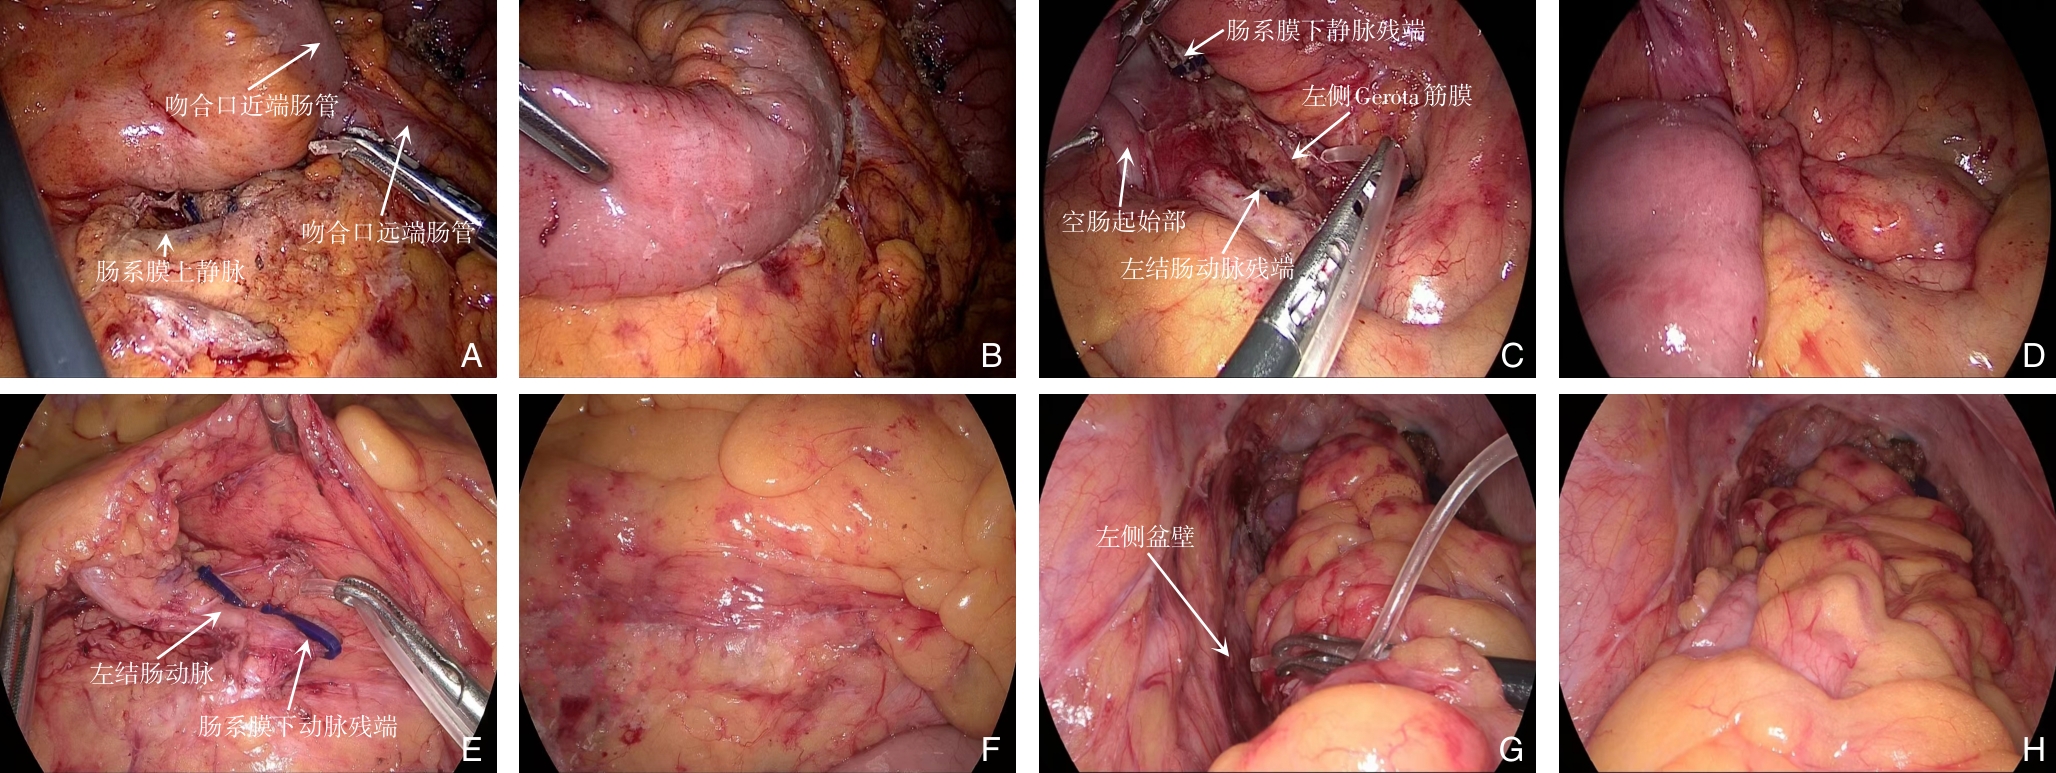

摘要:腹腔镜内括约肌切除术(ISR)是实现超低位直肠癌极限保肛的重要术式。本文基于团队400例手术经验,围绕手术一些关键难点提出系统优化策略。针对括约肌间隙游离困难,采用“折刀位经肛优先”策略,改善盆底暴露并降低环周切缘阳性风险;为预防降低吻合口漏的发生,探索ISR联合改良Bacon(Turnbull-Cutait)延期吻合方案,实现“安全免造口”;对吻合口大范围裂开,建立造口治疗师参与的全程管理体系,并开展经肛“U”形修补以促进吻合口快速愈合;在功能重建方面,尝试经腹肛提肌成形术以增强盆底支撑、改善控便功能。初步实践表明,这一系列策略有助于在ISR术中实现肿瘤根治与功能保护的平衡,为超低位直肠癌保肛治疗的规范化与个体化提供了新的思路,但仍需要更多高质量临床研究进一步证实。